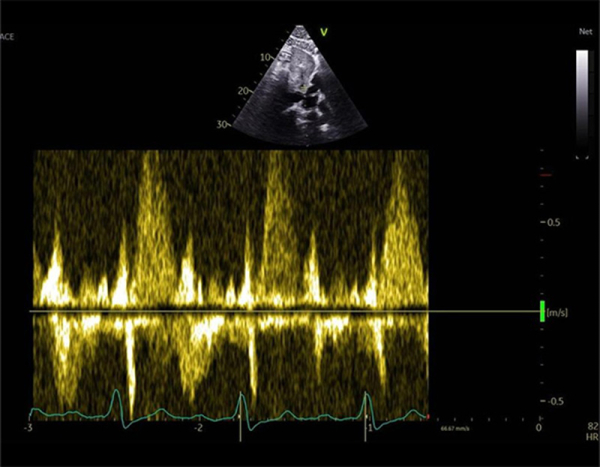

FEVG 35%, hypokinésie diffuse, pas de valvulopathie aortique ni mitrale.

VD non dilaté, normokinétique mais IT désormais laminaire avec reflux dans les veines sus hépatiques.